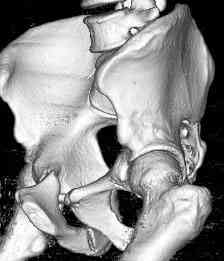

Уважаемые коллеги! опять вопрос по повреждению таза. Больной получил производственную травму 10 дней назад - удар балкой около 3 тонн в область верхней трети правого бедра и лона.

Был диагностирован перелом "типа бабочки" и повреждение уретры. Сделана цистостома. У насв отделении 3 дня. Имеется огромная флюктуирующая гематома с "галифе"-образной деформацией обеих бедер. Пнкционно эвакуировали в несколько приемов из подфасциальных полостей на бедрах около 3 литров геморрагического отделяемого с последующей эластической компрессией. При пункциях выявлено сообщение полостей на бедрах - видимо через поравннуюдиафрагму дна и полость таза - при удалении крови справа уменьшался объем левого бедра. Какой то активности проявялять покабоимся - аппаратная фиксация через отслоенные ткани представляется чреватой нагноением, открытая фиксация в условиях такой гематомы тоже не радует. Хотелось бы услышать ваше мнение

можно полечить в 2 этапа:как правило в области гребней гематомы все же не бывает, если гребни "свободны", то можно ограничиться на первом этапе передней рамой, вводя стержни через них (повреждение ротационно-нестабильное), затем после лечения отслаивающего повреждения Morel-Lavallee, выполнить открытую репозицию, внутреннюю фиксацию, возможно вместе с урологами. Тактику возможного лечения этой

18.12. - отдельное спасибо еще раз А.В.Рункову- больного оперировали (А.В.Рунков) - произведен остеосинтез аппаратом - фиксация за крылья, два стержня в лонные кости и репозиция (почти полная) снимки будут чуть позже.